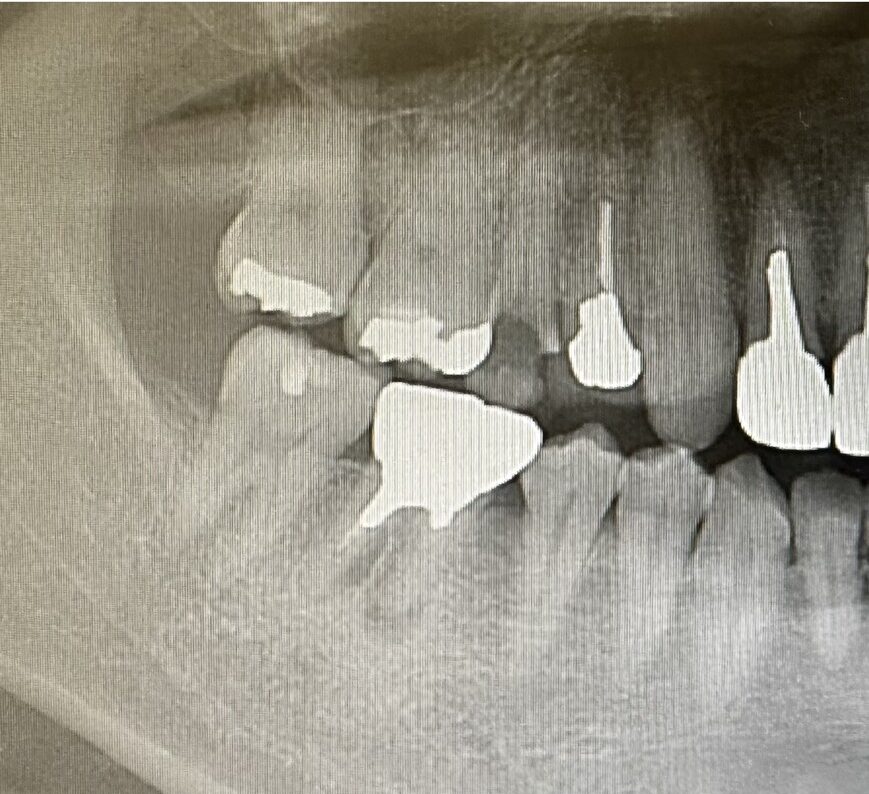

当院ではそのようなことがないよう初診時、治療開始前の説明を大事にしています。資料や写真、レントゲンを使って患者さまご自身にも出来る限りわかりやすくご説明させていただきます。

寿命を延ばしていく治療レントゲンやCT、口腔内写真、歯周ポケット検査など各種検査結果から、患者様一人ひとりに最適なむし歯・歯周病予防ケアをご提案します。

神経をできる限りとらず、

歯の寿命を延ばします歯がズキズキ痛い、ものすごい歯がしみるなどで「神経を取りましょう」と言われた経験がある方もいらっしゃると思います。しかし神経を取ると歯はかなり抜歯に近づきます。大きなむし歯でも神経を残せるケースも多くあります。的確な診断、高倍率の拡大鏡によりしっかり見える状態でむし歯のみを削り、むし歯以外の歯をできる限り削らず、適切な治療により歯の神経・血管をできる限り守ります。

治療の見える化

当クリニックが大切にしているのは、「10年後、20年後の患者様の将来」を見据えた治療です。お口の中は常に変化しているため、その歯を残すことが5年後や10年後に悪影響を及ぼす恐れがある場合は、今のうちの治療を検討する場合もあります。

最新のレントゲンや

CTなどによる検査 -